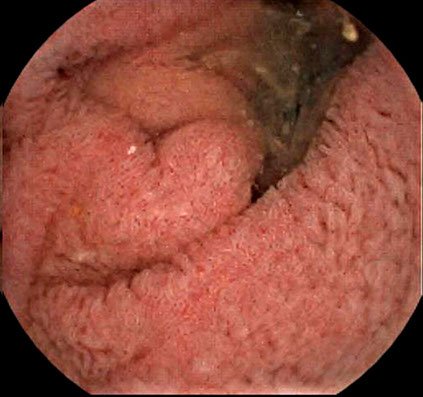

Case Gallery

ICE RGB Mode separates different RGB spectrums, gives you a more detailed view for mucosa and capillaries.